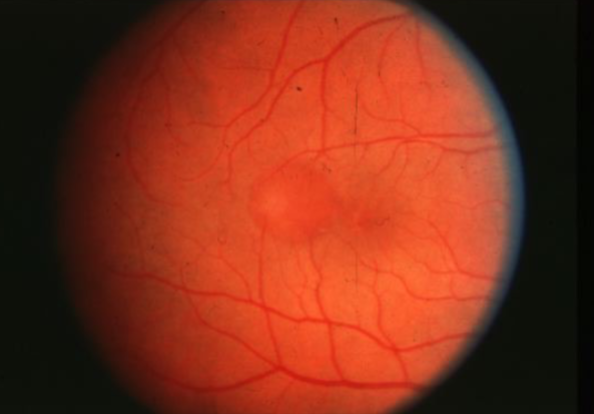

geographic or central areolar RPE atrophy

a form of dry AMD consisting of large areas of GA of the RPE

histologic: the area of GA is associated w/ focal loss of the retinal receptor cells, RPE, & choriocapillaris

5-10% of pts w/ AMD lose central vision as a result of this form of AMD

one or more sharply circumscribed geographic areas of atrophy of the RPE & retinal in the posterior pole

central vision is slow & progressive as the atrophic concentric area enlarges

bilateral, symmetric

20% of these pts will develop CNVM in the 2nd eye

FA shows varying degrees of loss of the choriocapillaris w/in the area of GA